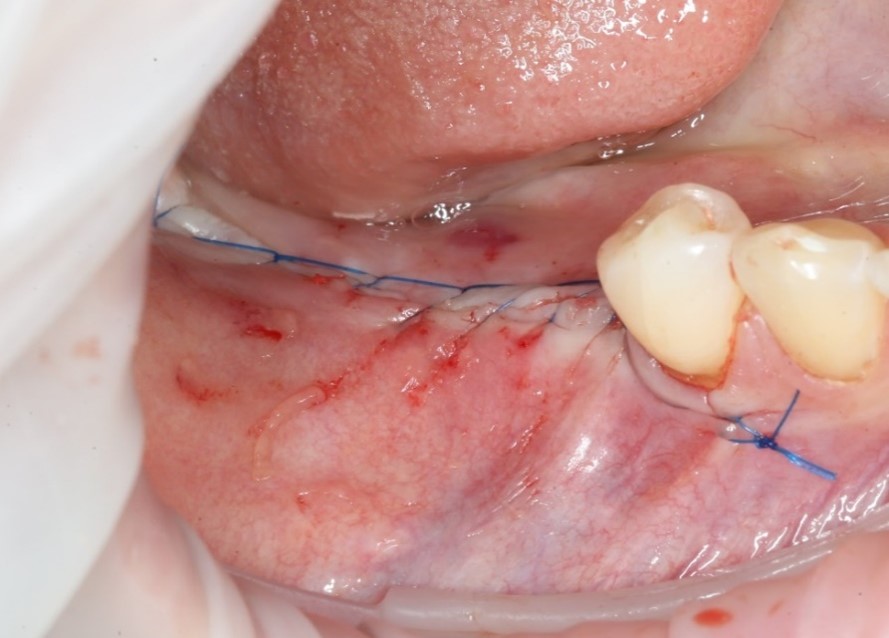

Мягкая ткань восстанавливается намного быстрее, чем костная. Для того, чтобы десна не проросла сквозь костный материал, его необходимо укрыть специальной рассасывающейся мембраной:

Мембрана помещается между десной и костью, добавляются остатки костной стружки:

И весь этот бутерброд укрывается ею, как одеялком:

Время накладывать швы (ножницы и иглодержатель):

Используется шовный материал – монофиламент. Нерассасывающаяся нитка, наподобие лески. В отличие от рассасывающихся швов, эта нить не скапливает на себе налет и остатки пищи, что особенно важно в случае с операциями.

Операция закончена:

Операция, классически, заканчивается наложением швов: